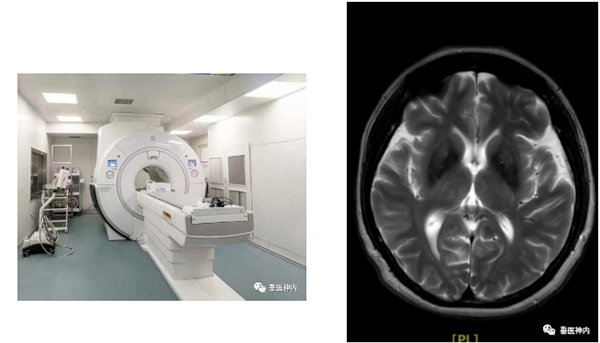

二、磁共振成像(MRI)

MRI是一种断层成像技术,它利用磁共振现象从人体中获得电磁信号,并重建出人体信息,对软组织分辨能力高于CT数倍,可比CT更有效和早期地发现病变,对颅脑、脊柱和脊髓等解剖和病灶的显示优于CT。磁共振血管成像借其“流空效应”,可不用血管造影剂显示血管结构。缺点是核磁共振检查室内存在非常强大的磁场,因此体内留有某些金属、安装心脏起搏器者不宜;因检查所需时间较长,对病情危重、幽闭恐惧的患者不宜。由于钛金属不受磁场的吸引,因此体内有钛金属内固定物的患者可以进行核磁共振检查。